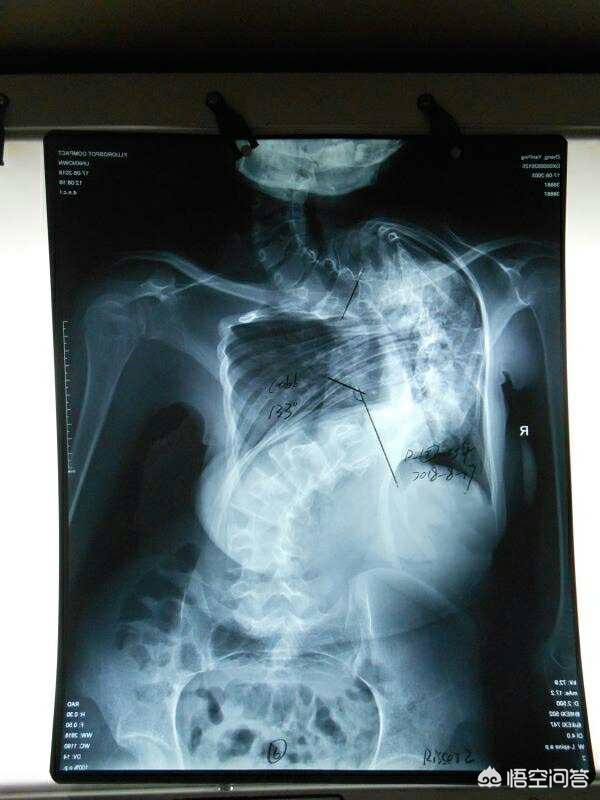

1,结构性脊柱侧弯,就是先天性发育缺陷,出现椎体结构问题,严重的从婴儿时就会出现,随身体生长越来越严,角度有可能在100度以上,身体明显变形扭曲,需要手术结合长期的康复训练调整,减少其它后遗症的发生。

这是比较严重的结构性脊柱侧弯,达到了133度,内脏位置和功能都受到影响。